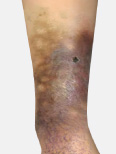

Left untreated, varicose veins cause increased pressure of pooled blood in leg veins. Fluid leaks out of these veins and may result in painful swelling and discoloration of skin known as hyperpigmentation. Inflammation of skin may cause severe itching, burning and redness.

• Lipodermatosclerosis

Lipodermatosclerosis

Continued inflammation of the skin over time causes the skin to become firm and leathery. Patients feel increased tenderness of the skin. The stiffening and hardening of the skin is known as Lipodermatosclerosis.

Continued increased pressure of blood in the leg veins causes changes to the skin that are typically noticed in the mid-calf to the ankle area. This condition, known as stasis dermatitis, is characterized by severe itching and redness of the skin followed by hyperpigmentation (discoloration of the skin due to deposition of iron pigments). This is followed by induration (thickening of the skin) and dermal fibrosis (scar tissue): a condition known as Lipodermatosclerosis. There may be atrophie blanche (smooth, ivory-white plaques surrounded by hyperpigmentation). The final stages of chronic venous insufficiency are related to the breakdown of skin and the formation of poorly healing leg ulcers (sores). There is a higher risk of local skin infection (cellulitis), sepsis (blood poisoning), and osteomyelitis (infection of the bone).